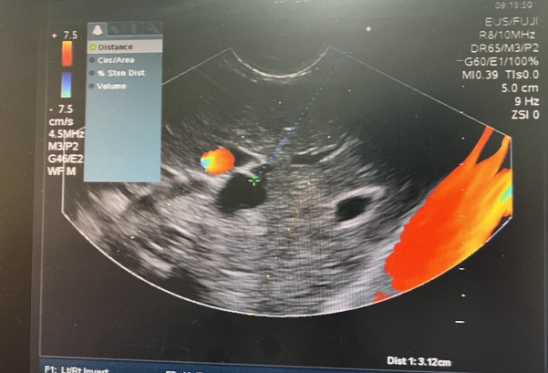

超声内镜定位胆内胆管

经过科内会诊,决定采用目前最先进的经超声内镜引导下进行胆汁引流(EUS- BD),祝喜萍凭借丰富的经验,在超声内镜引导下,顺利将导丝经胃壁穿入肝内胆管,再由胆总管经十二指肠乳头部进入十二指肠腔的“完美顺行”插管方式,成功放置胆道内支架,梗阻的胆汁顺利流出。术后,患者腹痛发热症状消失,2日后康复出院。

左图:超声内镜成功穿刺胆管并顺行留置导丝